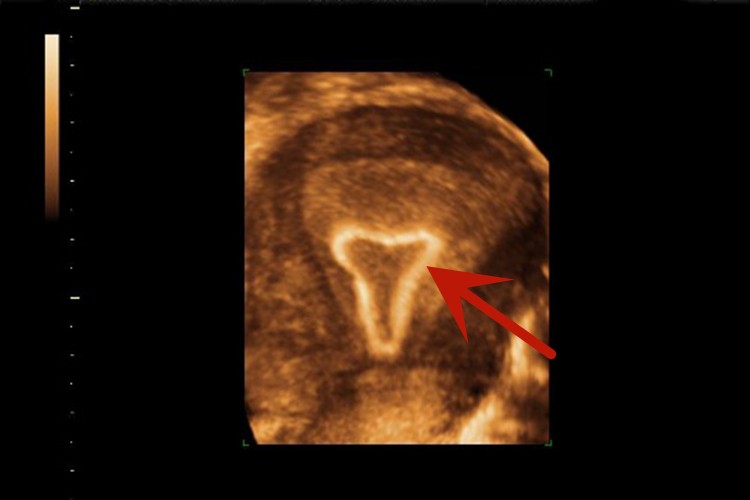

曼月乐环临床称为左炔诺孕酮宫内节育器,若已在宫内放置了这种节育器,可在彩超中显示,正常情况下,节育器的顶端接近子宫底。

曼月乐环临床称为左炔诺孕酮宫内节育器,是一种T形环,若已在宫内放置了这种节育器,通过彩超可以确定该节育器的位置。正常情况下,彩超显示宫内节育器的顶端接近子宫底,若显示宫内节育器的顶端距宫底较远,提示出现了节育器的下移。